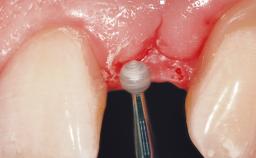

Late Flapless Placement of an Implant in a Maxillary Left Central Incisor Site

A 39-year-old male patient presented with a chief complaint of discomfort and gingival discoloration around his maxillary left central incisor. He was in good general health and was a non-smoker. His past dental history was significant because of the traumatic fracture of tooth 21 in a sporting accident at age 13. Initial dental treatment included endodontic therapy and a full-coverage restoration. The patient became symptomatic 5 years later, when structural failure of the tooth resulted in the dislodgment of the crown. Endodontic retreatment, apical surgery, and post-and-core restoration were performed.

Bone Augmentation Horizontal|Staged

Soft Tissue Grafting Simultaneous

Bone Volume Deficient horizontally, requiring prior grafting